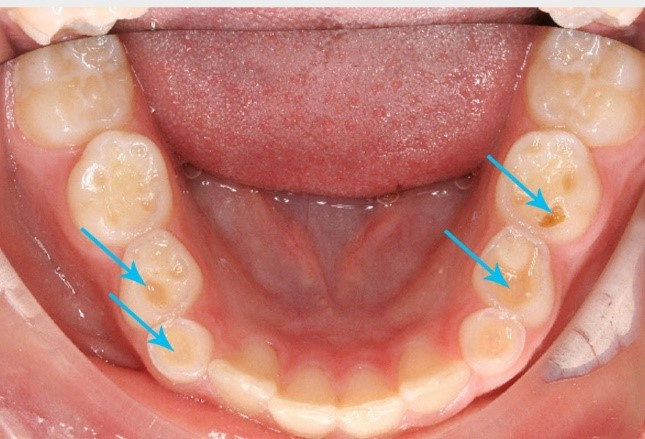

• تآكل أو تشقق في الأسنان

• تآكل الأسنان وقصرها

• تصدّع أو كسر في الأسنان

• مشاكل جمالية في مظهر الأسنان والابتسامة